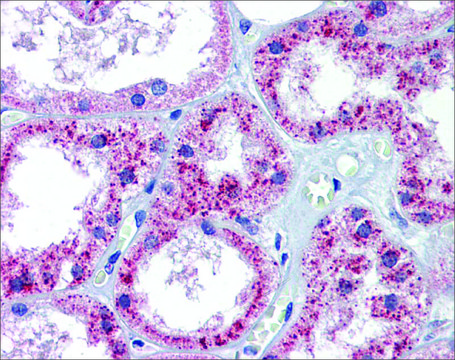

Anti-PTCH1 antibody produced in rabbit has been used in Flow cytometry/Cell sorting. It is suitable for western blotting at a concentration of 0.25μg/ml and for immunohistochemistry of paraffin-embedded tissue sections at a concentration of 4-8μg/ml.